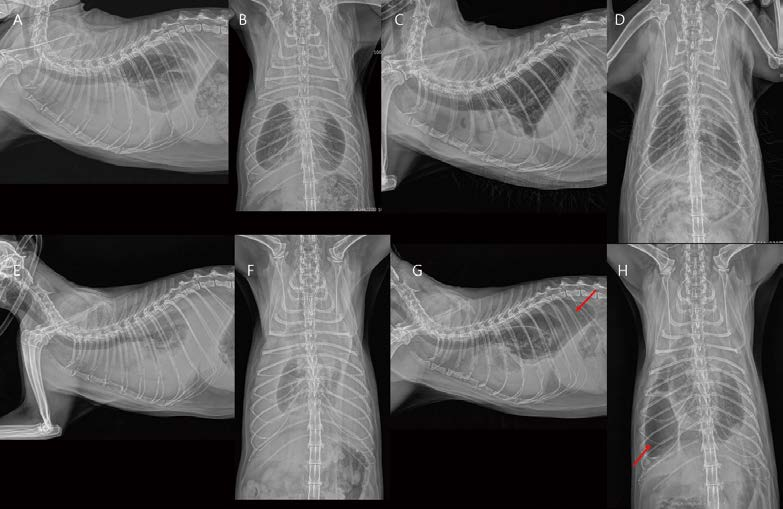

<여기서 잠깐 비교 증례!>

[대한수의사회지 24.png

잘 숨어 있는 다른 폐종양 환자를 비교해 보면, 이 환자는 accessory lung lobe의 adenocarcinoma로 인해 CdVC의 부분적 협착이 발생했고, 이로 인해 흉복수가 생기기 시작한 환자입니다. 흉부에서 midline에 인접한 병변 역시 종격 구조물에 의해 잘 숨어 있기 때문에 흉부방사선 검사 판독에 있어 좀 더 세심하게 판독하려고 노력해야 할 것 같습니다.

개와 비교 시, 고양이 원발 폐종양의 digits로의 전이가 좀 더 잘 관찰되어서 Lung digit syndrome 이라는 용어를 일반적으로 쓰고 있지만, 고양이에서 폐종양은 digit 뿐만 아니라, 전신 여러 군데로 전이가 잘 된다고 알려져 있습니다. MODAL syndrome(Muscle/ocular/digit/aorta/lung) 용어가 좀 더 임상적으로 활용되면 좋을 것 같습니다. 다음 고양이는 pulmonary adenocarcinoma가 전지, 후지 근육으로 전이된 MODAL syndrome 환자입니다.